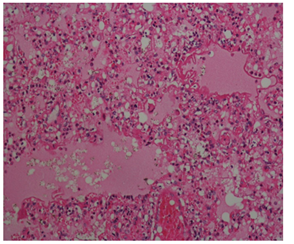

In the histopathological examination report obtained after the autopsy performed in the Morgue Department of Adana Forensic Medicine Group Presidency; ‘Edema, atelectasis, hyaline membranes, haemosiderin-loaded macrophages in large areas in the lungs, acute respiratory distress syndrome compatible appearance (Figure 1). Liver, kidney, spleen, heart, thymus, brain, brain stem and cerebellum congestion are detected and it is stated that the death of the person has an acute respiratory insufficiency syndrome resulting in anaphylactic reaction result related to insect bite. In our case; history, investigation information and histopathological examination were taken into account when ARDS was diagnosed.